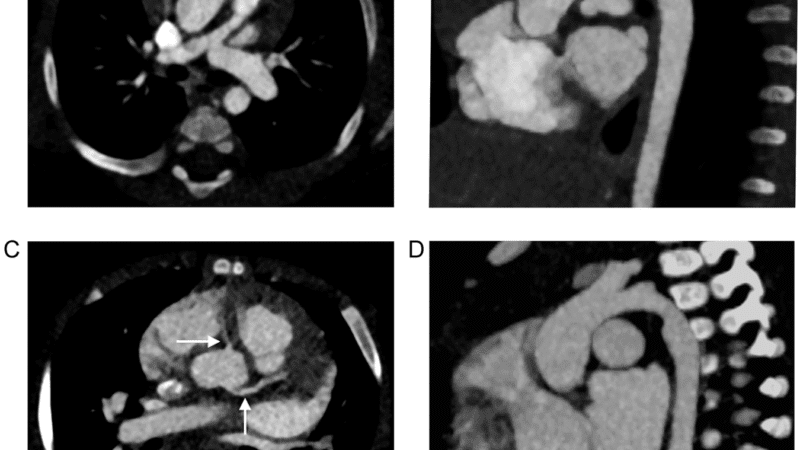

This improvement particularly benefits:

- Coronary stent evaluation

Clinical PCCT systems achieve pixel sizes of 250 micrometers in standard mode10 and 150 micrometers in ultra-high-resolution mode8,9 compared to conventional CT’s typical 240-500 micrometer resolution.